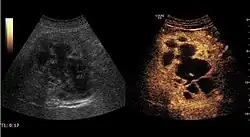

HCC appearance on 2D ultrasound is that of a solid tumor, with imprecise delineation, with heterogeneous structure, uni- or multilocular (encephaloid form). An "infiltrative" type is also described which is difficult to discriminate from liver nodular reconstruction in cirrhosis. Typically HCC invades liver vessels, primarily the portal veins but also the hepatic veins . Doppler examination detects a high speed arterial flow and low impedance index (correlated with described changes in tumor angiogenesis). The spatial distribution of the vessels is irregular, disordered. CEUS examination shows hyperenhancement of the lesion during the arterial phase. During the portal venous phase there is a specific "wash out" of ultrasound contrast agent (UCA) and the tumor appears hypoechoic during the late phase. Poorly differentiated tumors may have a stronger wash out leading to an isoechoic appearance to the liver parenchyma during portal venous phase. This appearance was found in approx. 30% of cases. The described changes have diagnostic value in liver nodules larger than 2 cm.

Ultrasound is useful in HCC detection, stadialization and assessing therapeutic efficacy. In terms of staging related to therapy effectiveness, the Barcelona classification is used which identifies five HCC stages. Curative therapy is indicated in early stages, which include very early stage (single nodule <2 cm), curable by surgical resection (survival 50-70% five years after surgical resection) and early stage (single nodule of 2–5 cm, or up to 3 nodules <3 cm) which can be treated by radiofrequency ablation (RFA) and liver transplantation. Intermediate stage (polinodular, without portal invasion) and advanced stage (N1, M1, with portal invasion) undergo palliative therapies (TACE and sorafenib systemic therapy) and in the end stage only symptomatic therapy applies.